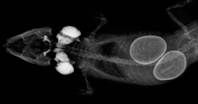

Legenot bei Reptilien (2016)

Tulpen blühen, Vögel zwitschern und Reptilien sterben - Willkomen Frühling! (mehr anzeigen)